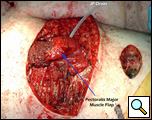

Eleven months later, he presented with a several month history of a painful fixed, firm mass over the pectoral area of the left chest and a smaller mass inferior to this (Figure 1). CT scan demonstrated a new 2 cm nodule in the left upper lobe associated with an anterior chest wall mass six centimeters in size in addition to bilateral new pulmonary nodules (Figure 2). The mass was tethered to the skin and in danger of eroding through it. The patient underwent en-bloc resection of the chest wall and adjacent lung (Figures 3a-c). The resulting defect (Figure 4a) was reconstructed with 2 mm Gore-Tex patch (Figure 4b) and pectoralis major muscle flap (Figure 4c) with primary skin closure (Figure 4d). The pathology revealed metastatic chordoma (Figures 5a-d). The patient recovered well, leaving the hospital on the sixth postoperative day.